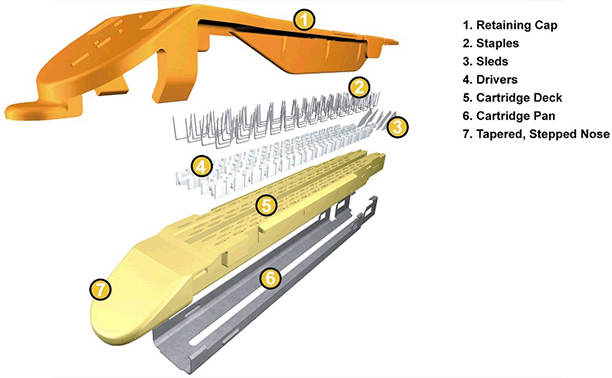

術中に使用しているデバイス

自動縫合器

カートリッジの仕組み